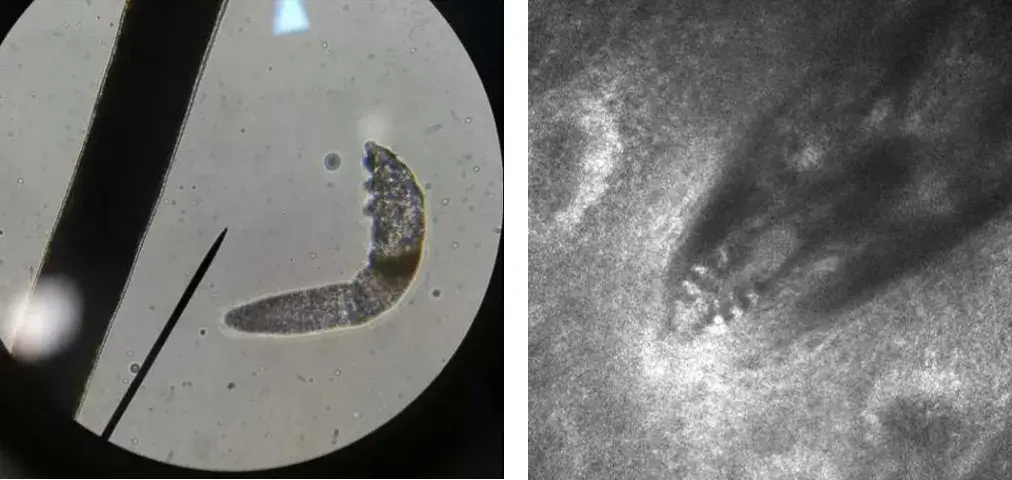

用显微镜聚光器向下(a)和向上(b)拍摄的犬蠕形螨.

图片尺寸660x437